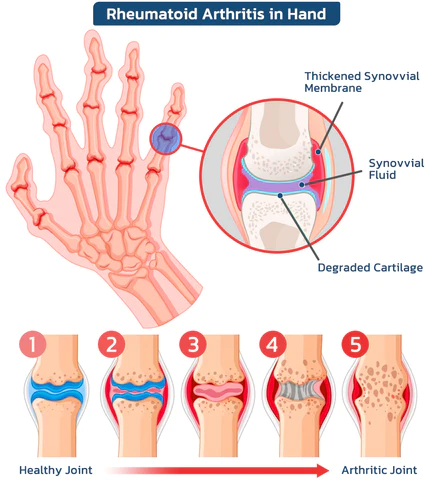

The dangers of arthritis?

According to estimates by the World Health Organization (WHO), approximately 300 million people worldwide suffer from arthritis. Less severe cases include arthritis, rheumatism and gout, with symptoms including pain, stiffness, swelling, difficulty with movement, fatigue and loss of range of motion. Severe cases can lead to joint deformities, fever and severe joint pain, resulting in long-term pain and disability. In extreme cases, orthopedic conditions can even lead to life-threatening complications.

Common Orthopedic Joint Symptoms

Arthritis refers to inflammatory diseases that occur in the joints and surrounding tissues of the human body and are caused by inflammation, infection, degeneration, trauma, or other factors. They can be divided into dozens of types. Clinical manifestations include redness, swelling, heat, pain, dysfunction, and deformity of joints, which can lead to joint disability and affect the quality of life of patients.

According to statistics, osteoarthritis affects half of the population over the age of 50 in the United States and 90% of women and 80% of men over the age of 65. The life expectancy of those with severe symptoms is shortened by about 10 to 15 years.